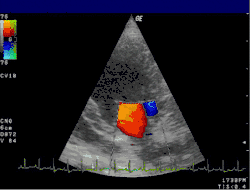

Doppler echocardiography is a procedure that uses Doppler ultrasonography to examine the heart.[1] An echocardiogram uses high frequency sound waves to create an image of the heart while the use of Doppler technology allows determination of the speed and direction of blood flow by utilizing the Doppler effect.

An echocardiogram can, within certain limits, produce accurate assessment of the direction of blood flow and the velocity of blood and cardiac tissue at any arbitrary point using the Doppler effect. One of the limitations is that the ultrasound beam should be as parallel to the blood flow as possible. Velocity measurements allow assessment of cardiac valve areas and function, any abnormal communications between the left and right side of the heart, any leaking of blood through the valves (valvular regurgitation), calculation of the cardiac output and calculation of E/A ratio[2] (a measure of diastolic dysfunction). Contrast-enhanced ultrasound-using gas-filled microbubble contrast media can be used to improve velocity or other flow-related medical measurements.

An advantage of Doppler echocardiography is that it can be used to measure blood flow within the heart without invasive procedures such as cardiac catheterization.